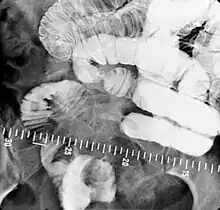

Enteroclysis

Enteroclysis is also known as small bowel enema.[21] It has been largely replaced by magnetic resonance enterography/enteroclysis[13] and computed tomography enterography/enteroclysis.[22]

In addition to fasting for 8 hours prior to examination, a laxative may also be necessary for bowel preparation and cleansing.[12] The main aim of this study is to distend the proximal bowel through infusion of large amount of barium suspension. Otherwise, the distension of distal small bowel is generally similar with small bowel follow-through. Therefore, there is a need to pass a tube through the nose into the jejunum (nasojejunal tube) to administer large amount of contrast. This can be unpleasant to the subject, requires more staff, longer procedural time, and higher radiation dose when compared to small bowel follow-through. The indications for enteroclysis are generally similar to small bowel follow-through. Barium suspensions such as diluted E-Z Paque 70% and Baritop 100% can be used. After that, 600 ml of 0.5% methylcellulose is administered after 500 ml of 70% barium suspension is given. Bilbao-Dotter tube and Silk tube can be used to administer barium suspension. The subject should be fasted overnight, any antispasmodic drugs should be stopped one day before the examination, and Tetracaine lozenges can be used 30 minutes before the procedure to numb the throat for nasojejunal tube insertion.[13]

The filling of the small intestines can be viewed continuously using fluoroscopy, or viewed as standard radiographs taken at frequent intervals. The technique is a double-contrast procedure that allows detailed imaging of the entire small intestine. However, the procedure may take 6 hours or longer to complete and is quite uncomfortable to undergo.[23]